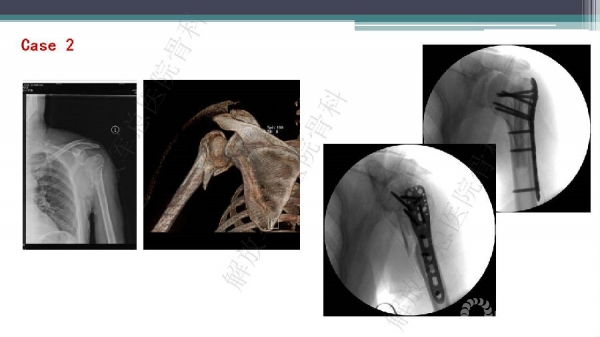

导 语:肱骨近端骨折仍是最常见的骨科损伤之一,尤其好发于老年人群。移位型肱骨近端骨折通常需要手术治疗,但是由于骨折粉碎、骨质较差,手术治疗往往会比较困难。随着锁定钢板的发明,使得并发症显著降低。但仍存在一些问题,对于内侧皮质不连续缺乏内侧可靠支撑,合并老年骨质疏松的病人,锁定钢板吊臂样结构就无法满足力学要求,随着康复锻炼可能出现断板、断钉、螺钉切出肱骨头等并发症。本期解放军总医院骨科专家们对老年肱骨近端骨折的问题与创新手术技术进行了详细讲解。